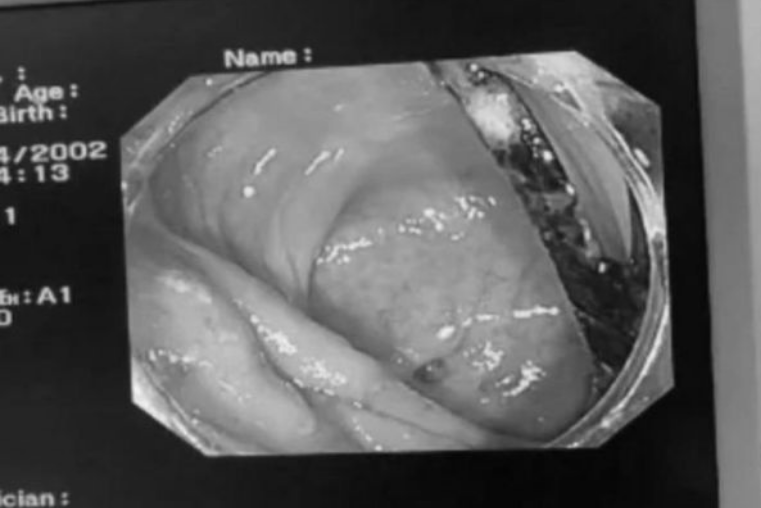

Aylarla keçməyən mədə ağrısından əziyyət çəkirdi! Bağırsaqlarından gorün nə çıxdı - Həkimlər də təəccübləndilərÇinin Quandun əyalətinin Foşan bölgəsində adı açıqlanmayan bir xəstə aylardır davam edən mədə ağrısı səbəbiylə xəstəxanaya yerləşdirilib. Endoskopik əməliyyat zamanı xəstənin bağırsağında yad cisim aşkar edilib.

Sonxeber.az xarici KİV-ə istinadən xəbər verir ki, təxminən 8 sm uzunluğunda olan yad cismin bağırsaq divarına ilişib iltihab və anevrizma əmələ gətirdiyi bildirilib.

Yad cismin plastik çəngəl olduğu müəyyən edilib. Çəngəl səbəbindən bağırsaqların ciddi zədələndiyi bildirilib.